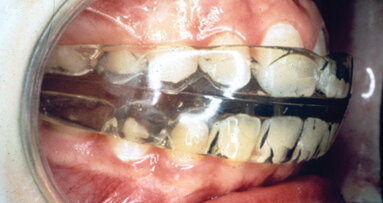

By association, the orthodontist can be drawn in to the TMJ/D issue. There is no proven link between orthodontic treatment and TMJ disorder; however, the position and function of the condyles is directly controlled by the oral structure (see illustration above). Therefore, the orthodontist’s actions can influence the TM joints. This is a question of anatomy, not law.